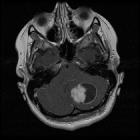

These tumors are usually large, well-circumscribed, lobulated and may have solid or cystic components with no or minimal surrounding edema. They are typically described as H-shaped as they expand from the midline ( hypothalamic and optic chiasma region )into both temporal lobes. Hemorrhagic components may be present. CSF dissemination can also be seen.

MRI

Reported signal characteristics include:

- T1: isointense

- T2: usually hyperintense, reflecting its myxoid matrix

- GRE/SWI: approximately 20% show intratumoral hemorrhage

- T1 C+ (Gd): common and is usually in the solid component but can be also peripheral

- DWI/ADC: usually high ADC values (facilitated diffusion), reflecting its myxoid matrix